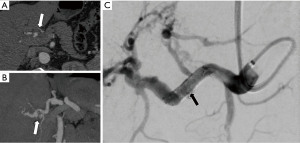

Splenic artery aneurysms account for 60% of all VAAs. A significant association has been observed with females, pregnancy, and portal hypertension. The majority (75%) are found in the distal portion, 20% in the middle section, and 5% in the proximal region. For fusiform aneurysms, endovascular repair using a covered stent or stent-assisted coil embolization is often the preferred approach, but this is only feasible for proximal or intermediate localization. Coil embolization is considered a safe and economical alternative with minimal risk of ischemic complications, even in cases of splenic artery occlusion, due to the presence of short gastric collaterals. Splenic infarcts may occur only when embolizing hilar or intraparenchymal aneurysms with vessel sacrifice, but these are typically limited, often clinically insignificant, and managed conservatively. The density of coil packing is essential to prevent aneurysm revascularization (49) (Figure 1).